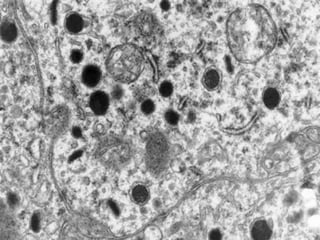

 Proliferación benigna del

epitelio escamoso

 Asociada a vph 2, 4, 40

 Hiperqueratosis, acantosis,

papilomatosis, coilocitosis y

prominentes gránulos de

queratohialina.

 Nódulo circunscrito, firme,

exofítico, usualmente único

de menos de 0.5 cm.

 Labio, paladar, alvéolo,

encía, lengua, etc.

Verruga vulgar cavidad oral Proliferación benigna del epitelio escamoso  Asociada a vph 2, 4, 40  Hiperqueratosis, acantosis, papilomatosis, coilocitosis y prominentes gránulos de queratohialina.  Nódulo circunscrito, firme, exofítico, usualmente único de menos de 0.5 cm.  Labio, paladar, alvéolo, encía, lengua, etc.